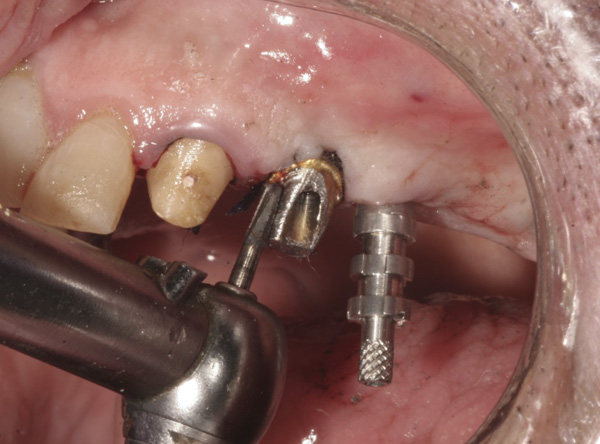

Results: A decision was made to re-prepare all of the abutments intraorally (Figure 3) so that all abutment margins would be at or below the gingival margin. (Of note, teeth Nos. 8 and 9, also shown in Figure 3, were later submerged for the case to be fully implant-supported.) While re-preparation greatly improved the esthetics of the final result, it required retraction cord placement, new impressions, and new castings.

Figure 3 Abutments re-prepared intraorally.

Figure 3

Figure 4 Following osseointegration of an implant at No. 12, recession was observed at the fixture-level impression stage of No. 13; it was decided to re-prepare the margins of the CAD/CAM custom abutment of implant No. 12. Retraction cord was placed prior to preparation to avoid tissue injury and improve visibility of both tooth No. 11 and the implant custom abutment margin. As expected, recession was greater along the distal side of abutment No. 12, adjacent to the healed extraction/newer implant site.

Figure 4